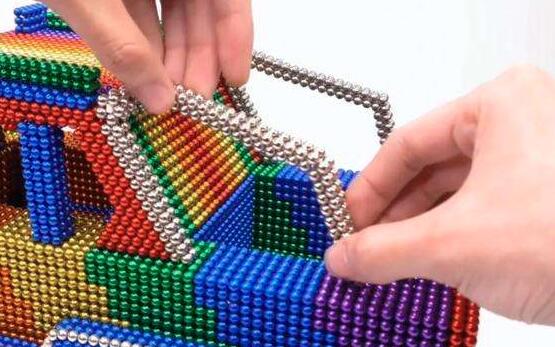

这一切的罪魁祸首,就是人人都可以买到的玩具磁珠(也叫巴克球)。

风靡起来的巴克球磁珠

最近两年这种从国外传进来的玩具,巴克球磁珠越来越受孩子的喜爱,不管是网上还是商场,超市,庙会,小卖部到处都有卖的。

这种玩具在国外是归类到成人减压玩具的,根本不是国内奸商忽悠的开发智力的玩具。

何先生就是从手机上看到徐州市儿童医院网站的一条报道,说是有孩子吞下磁珠,有引起肠梗阻、肠坏死以及肠穿孔可能,严重的还会危及生命,往往需要行胃镜检查或手术及时取出——这条信息引起了他的警惕。

“这种磁珠玩具我也给孩子买过的,她也经常拿着玩,不过最近几天没看见磁珠,那珠子去哪儿了。”

何先生说,他也担心宝贝女儿不小心将磁珠吞进肚子,就赶紧带着孩子到当地医院检查。腹部立位片显示,孩子上消化道里有金属异物征象。

为确保治疗效果,何先生随即带孩子转诊到徐州市儿童医院。经胃镜检查:胃腔内有两颗磁珠,从而确诊梦梦腹中的金属异物是磁珠。

“从片子上看,这些磁珠像是紧紧连在一起的,实际上,磁珠可能分布在不同的部位。”市儿童医院普外二科主任医师邹华新说,若幼儿分次吞入磁珠,珠子会随着胃肠蠕动向下移动,由于磁珠相互之间强烈的吸引力,不同部位的磁珠会对胃与肠管之间或肠管与肠管之间形成粘连和挤压,如此一来,很可能导致肠梗阻、肠穿孔或胃肠之间内瘘。

为避免磁珠在胃肠内引起的并发症,邹华新带领团队立即为梦梦进行了取珠手术。胃腔里取出2颗,十二指肠腔里取出20颗,术前影像资料上显示是25颗,还有3颗磁珠经过术中摄片结合体表定位明确在胃壁内,最后在胃壁肌层里取出剩余的3颗磁珠。

当把这25颗磁珠排放在一起时,医生邹华新也颇为惊讶:“这个小玩意的磁性还挺强的,最初想在胃镜下用钳子抓,怎么都抓不动,现在想摆在一起量个长度,也怎么捋不直。”他表示,幸好此次磁珠得以较早取出,否则时间拖得越久,磁珠就能导致胃穿孔、肠梗阻、肠穿孔或胃肠之间内瘘的并发症。

为人父母的长点心吧,不能孩子要什么就给买什么,要有自我判断能力,孩子小不懂事,尤其有些孩子喜欢把东西往嘴里放,大人可不能稀里糊涂的。